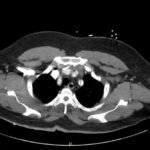

Acute aortic dissection is a life-threatening event caused by separation of the aortic layers that requires prompt management and surgical consultation. We present the case of a 53-year-old male who developed acute, severe chest pain radiating to his back at a community hospital and was transferred to a tertiary center for definitive surgical management. The patient’s aortic dissection was diagnosed via computed tomography angiography. He was started on rate-control and blood pressure medications, and was admitted emergently to the operating room. Emergency physicians should obtain immediate surgical consultation, promptly start medications for rate and blood pressure control, and administer analgesia in order to stabilize their patient and decrease the shear forces that would further propagate an aortic dissection.